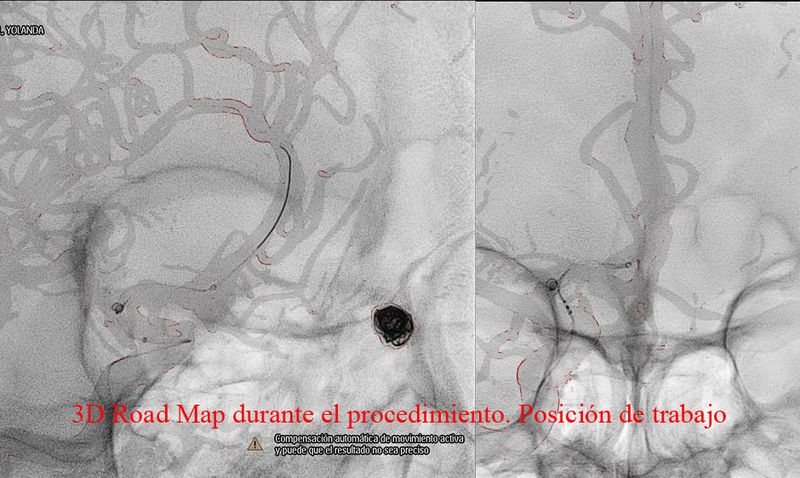

Aneurisma de arteria comunicante anterior